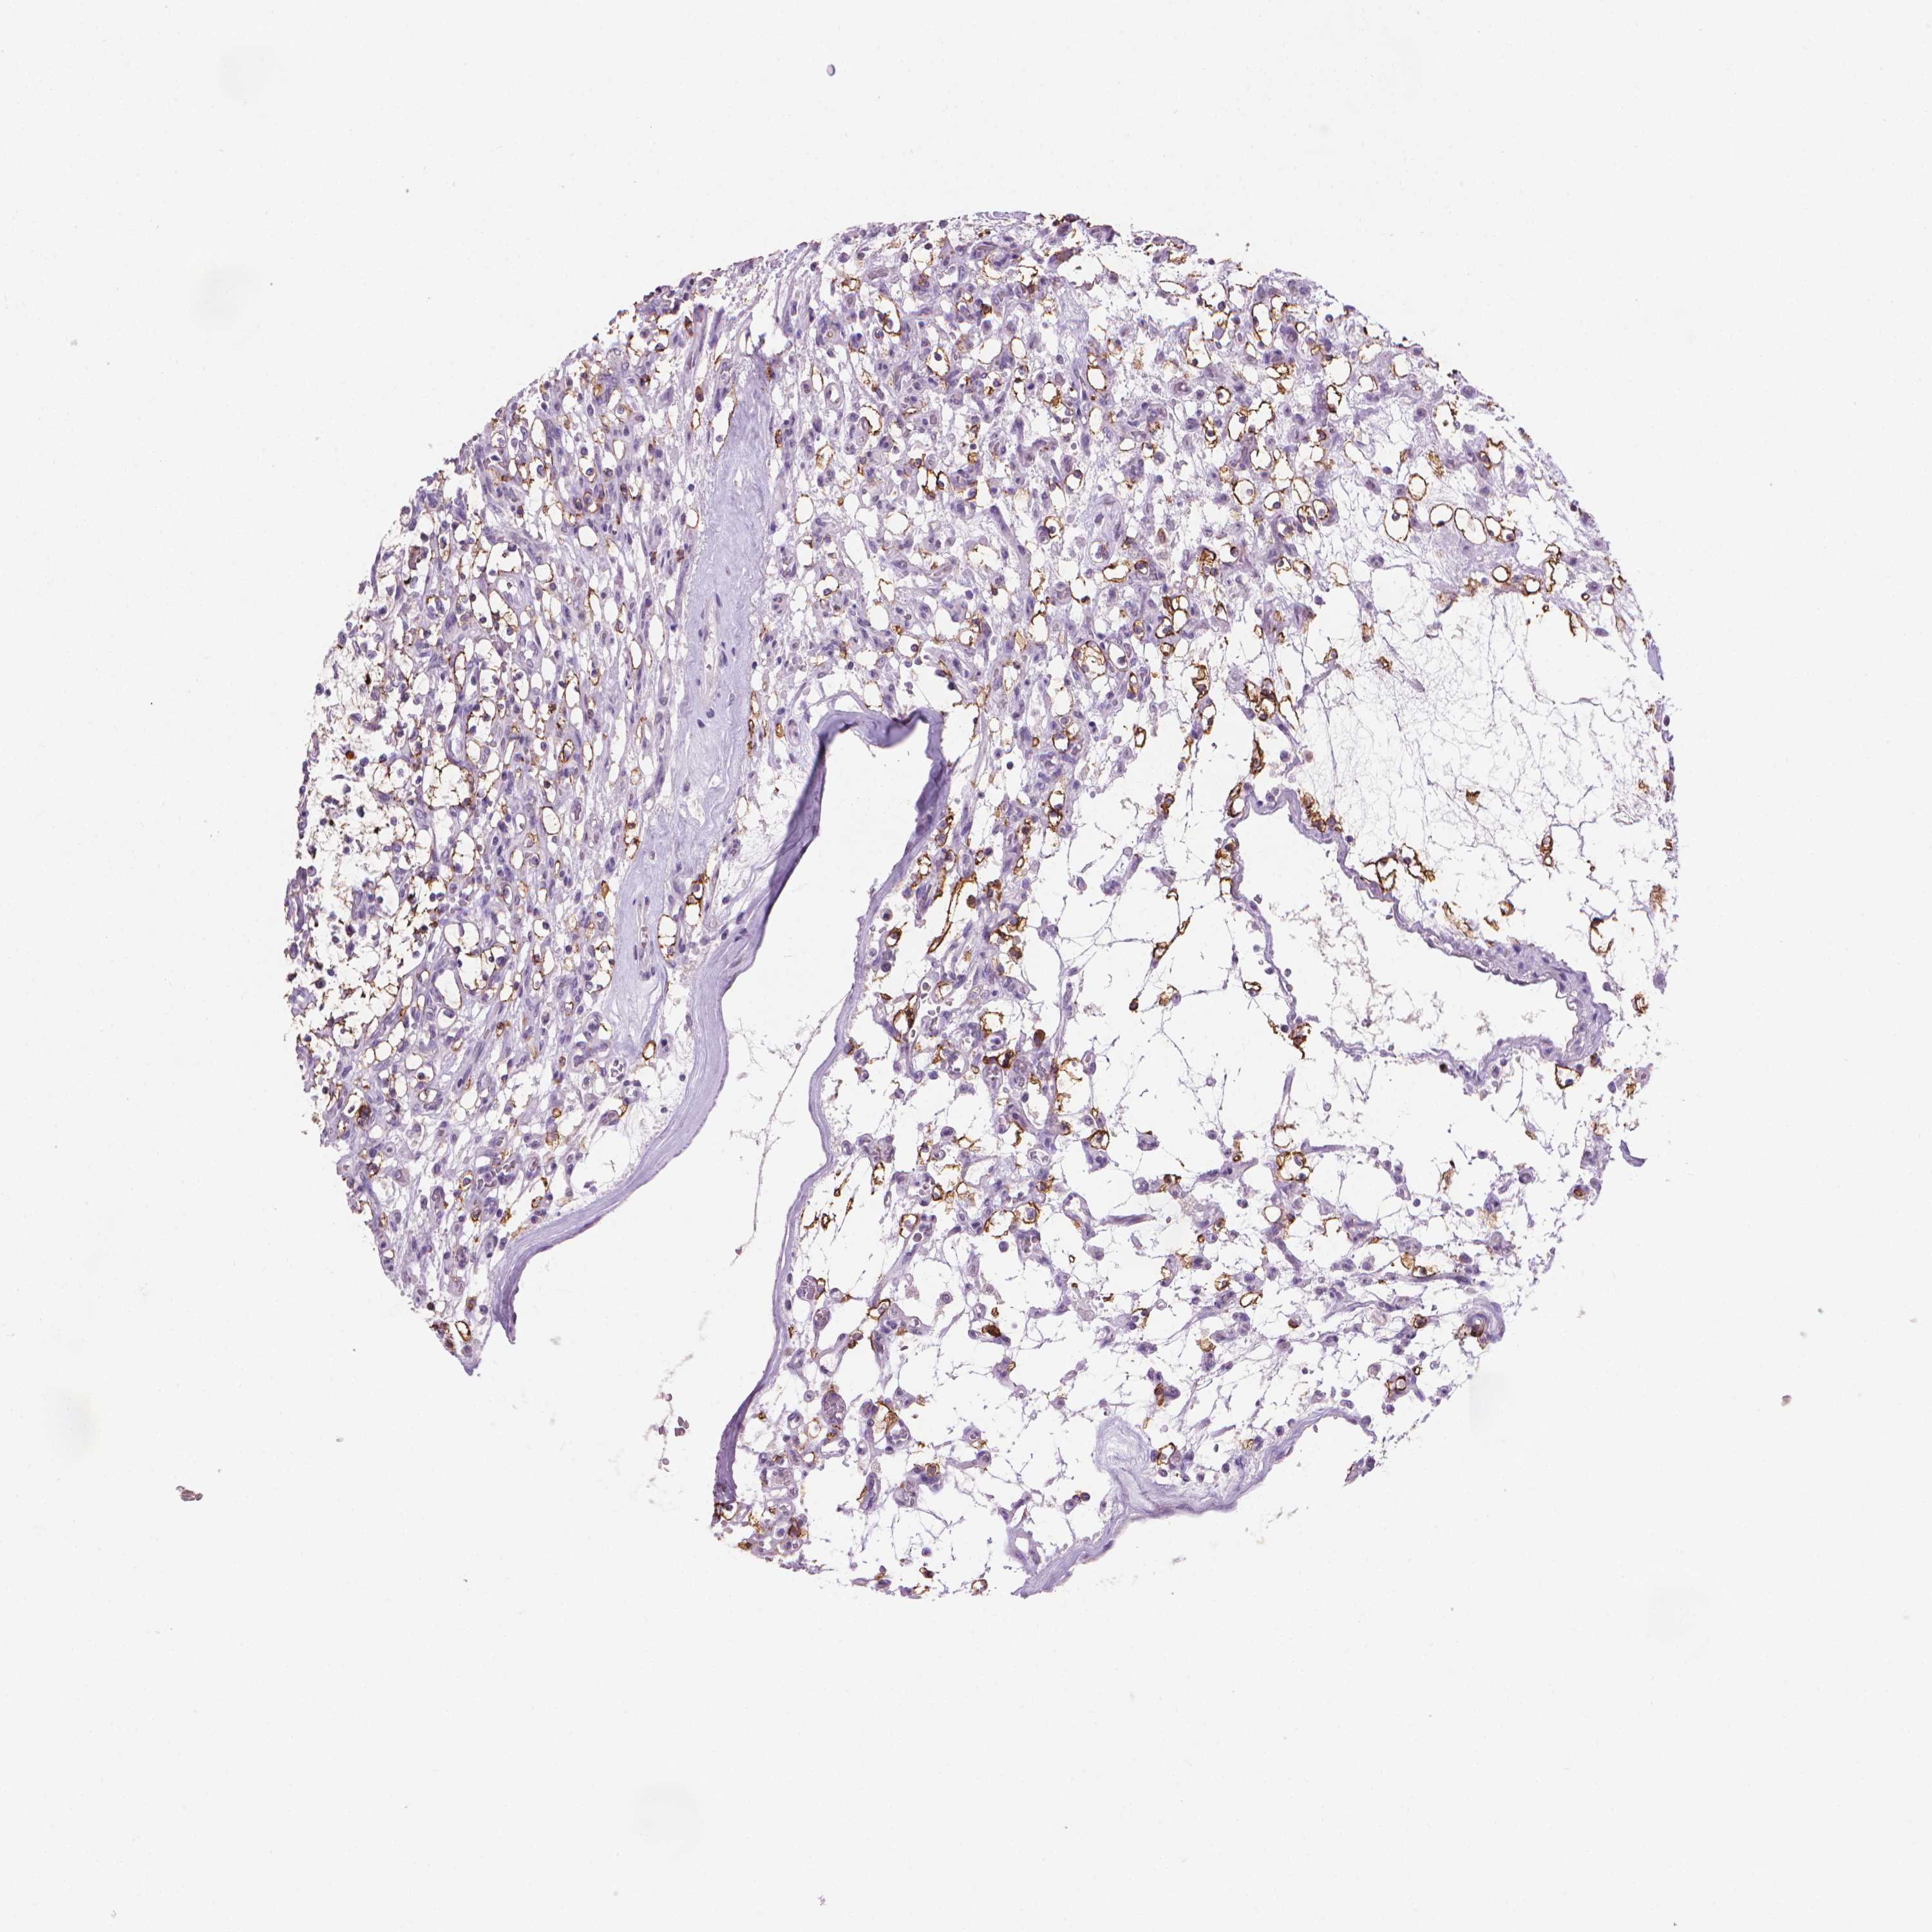

KIDNEY RENAL CLEAR CELL CARCINOMA (TCGA) - Interactive survival scatter ploti

MUC1 is potential prognostic, high expression is unfavorable in Kidney Renal Clear Cell Carcinoma (TCGA)

: 68.58

Average pTPM 106.2